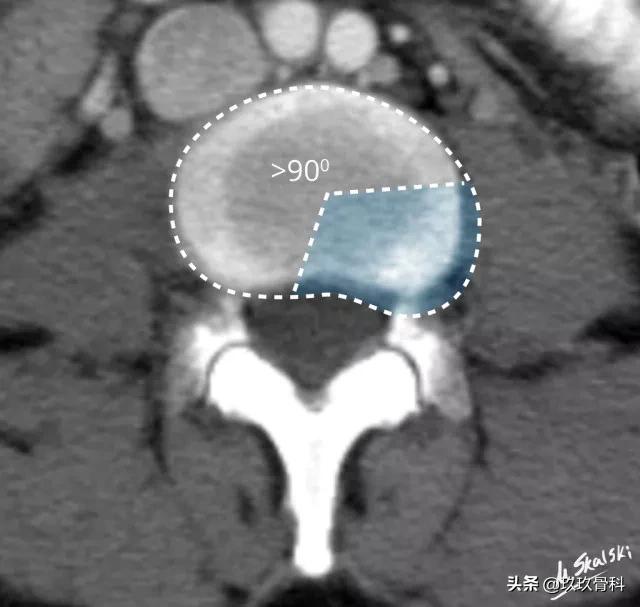

1. 椎间盘膨出(Disc bulge)

纤维环松弛但完整,髓核皱缩,表现为纤维环均匀超出椎体终板边缘。

图 3 椎间盘膨出的影像学定义为突出部分>椎间盘边缘的25%,或者突出的两边与髓核的中心的夹角>90°